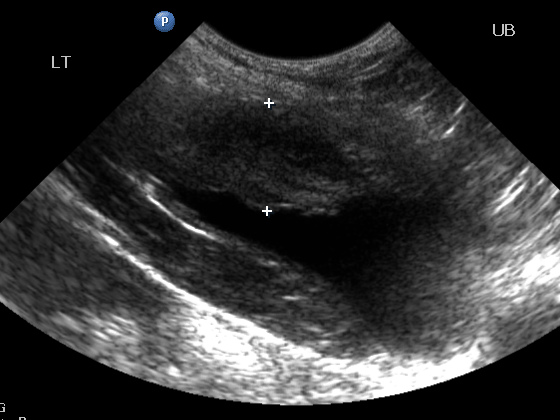

超音波是診斷膀胱腫瘤的第一個工具,除了檢查膀胱是否有腫塊出現之外,還可以評估是否有局部轉移的發生,不過嚴重的膀胱炎與膀胱腫瘤在超音波下難以辨認,所以還是必須依賴組織學切片。

超音波檢查: 此膀胱腫塊發生在前、中段膀胱,較少見。